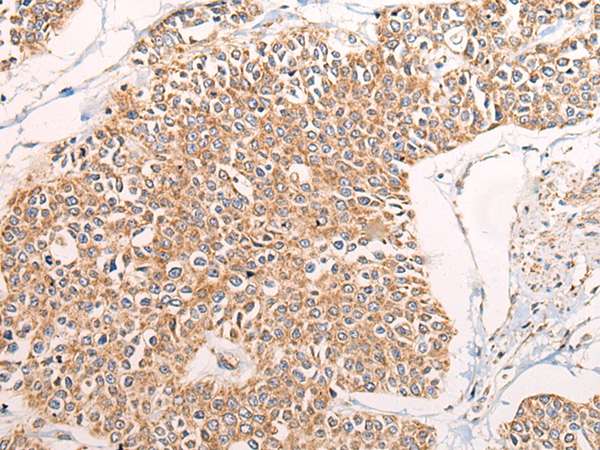

IHC positive control: |

Human prostate cancer and Human brain |

IHC Recommend dilution: |

40-200 |